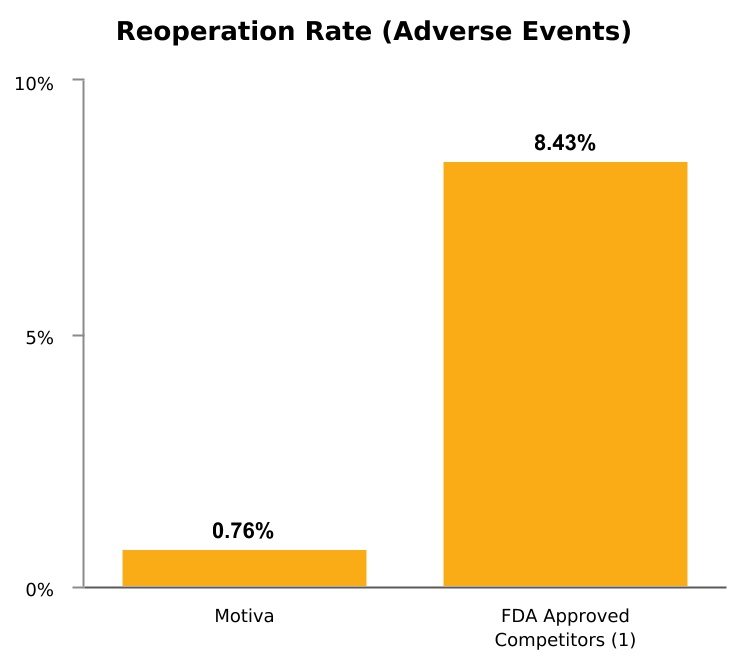

An independent study by Sforza et al., published in the peer-reviewed Aesthetic Surgery Journal in 2017, conducted at a single center, the Hospital Group Ltd.’s Dolan Park Clinic, or Dolan Park, in Bromsgrove, England, between April 2013 and April 2016, reported 5,813 consecutive cases of breast augmentation with Motiva Implants. This independent study was commissioned by Dolan Park’s medical director, Dr. Sforza, who is also a member of our medical advisory board and receives compensation from us in such capacity. The study, conducted by a group of 16 plastic surgeons at Dolan Park, reported overall rates of complication and reoperation of 0.76% over an interval of three years. Beginning in March of 2014, we started supplying our products to Dolan Park under a series of long-term supply agreements with Dolan Park’s affiliated companies. The last supply agreement expired in July of 2019. There were no serious adverse events and no cases of implant rupture for device failure, capsular contracture (Baker III/IV) in primary cases, double capsules, or late seromas. The authors presented consistent real-world data and believe that their free, three-year aftercare system is a strong method for patient retention and follow-up by eliminating any financial limitations for patients to return for follow-up

consultations if any issues occur. Anecdotally, the same group of surgeons utilizing the same aftercare system for the last seven years reported substantially different results utilizing other types of silicone breast implants (i.e., non-Motiva Implants). The overall revision rate for this group from 2010 to 2013 utilizing a different, macro-textured, FDA approved implant (N > 10,000) was 8.43%, which is more than 10 times higher than the rate for Motiva Implants reported in this analysis.

(1) Names of FDA approved competitors have not been published.